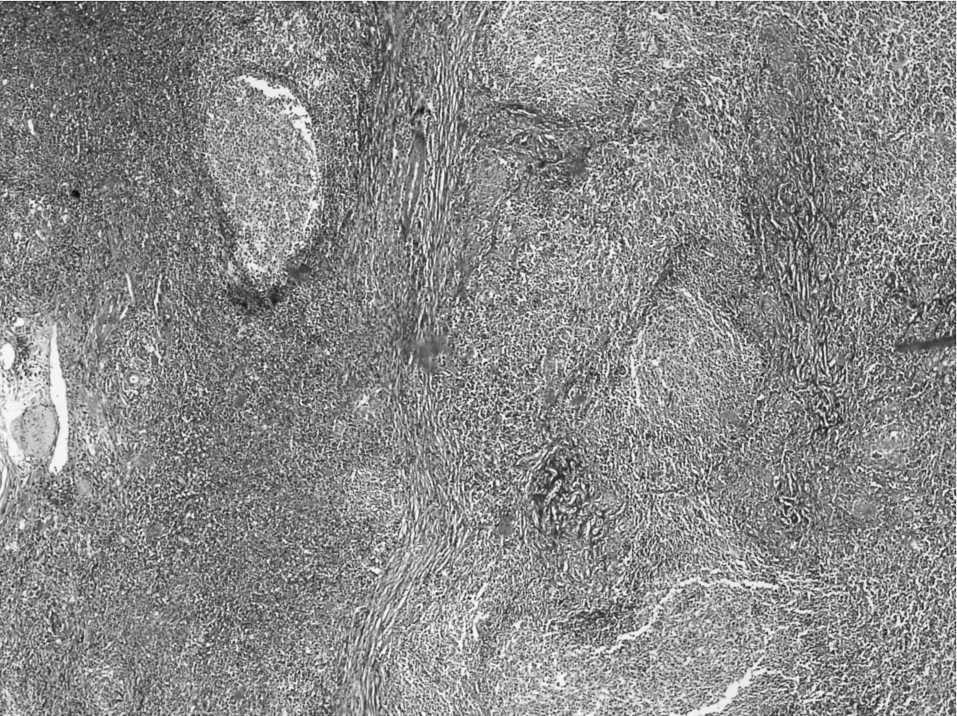

Mujer de 33 años, sin antecedentes médicos de interés, de origen magrebí. La paciente estaba asintomática. Hallazgo casual, por ecografía realizada por trastorno ginecológico, de una lesión ocupante de espacio en el segmento VI hepático confirmada por tomografía computarizada y resonancia magnética (RM) (fig. 1). Diagnóstico: masa hepática hipoecogénica en segmento VI con una ligera hiperseñal en secuencia T2 y un resalte periférico en la fase arterial tras la inyección de gadolinio. A pesar de que no se evidenció crecimiento de la lesión en una RM realizada a los 3 meses, se procedió a su extirpación quirúrgica. La punción-biopsia no fue concluyente, en ausencia de material adecuado. El hemograma fue normal: hemoglobina, 13,5; hematocritos, 40%; leucocitos, 7.020 con el 8,6% de linfocitos. La bioquímica sérica mostró los siguientes valores: proteínas totales, 5,8; colesterol, 104 mg/dl, lipoproteínas de baja densidad, 43,8 mg/dl; GOT, 288; GPT, 337; alfafetoproteína, 1,8 U/ml; CEA, 1,6 ng/ml; CA 19.9, 11,7 U/ml. Se descarta de entrada adenoma, hepatoma, colangiocarcinoma e hiperplasia nodular focal. Decisión terapéutica: segmentectomía del VI (fig. 2). Informe anatomopatológico: hiperplasia nodular linfoide hepática de 1,5 cm con márgenes quirúrgicos libres de infiltración tumoral (fig. 3); el resto del parénquima era de carácterísticas normales. A los 24 meses, la paciente está viva, en buen estado general y libre de enfermedad.

Fig. 3. Hiperplasia nodular linfoide (H-E, x200).

En el caso del seudolinfoma el diagnóstico es anatomopatológico y mediante técnicas inmunohistoquímicas, para comprobar que hay proliferación linfoide reactiva. Se presenta como una única lesión linfoide nodular y está reconocida como entidad propia; es obligatoria la diferenciación del linfoma de bajo grado4.

Se ha publicado muy pocos casos de HLR hepática. En una revisión de bases de datos electrónicas: MEDLINE, PubMed, EMBASE, Cochrane Library, Sinal, hay solamente 15 casos descritos hasta la actualidad. Generalmente, en esta afección no hay manifestaciones sistémicas asociadas. En nuestro caso, la paciente no presentaba hepatopatía crónica ni cirrosis. En algunos de los casos descritos, el diagnóstico se realizó en la pieza de hepatectomía previamente al trasplante. Son lesiones de hallazgo casual y radiológicamente aparece como masa hipervascular e hipoecoica5. Están bien delimitadas, se caracterizan por hiperplasia focal linfoide reactiva de aspecto polimórfico y poblaciones de células policlonales y agregados de linfocitos maduros, células plasmáticas y ocasionalmente fibrosis estromal6. La hialinización en áreas porta puede ser un hallazgo prominente, que puede imitar el tipo hialino-vascular de la enfermedad de Castleman7. El pronóstico es bueno ya que la totalidad de los pacientes tratados mediante cirugía exerética no han mostrado recidiva ni progresión.